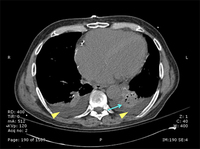

CT scan of a patient with a left lower lobe alveolar infiltrate (blue arrow), bilateral pleural effusions (yellow arrowheads), and right basilar atelectasis; notice the line separating the two shades of gray representing the infiltrate and the fluid

Consent obtained at University of Louisville, KY